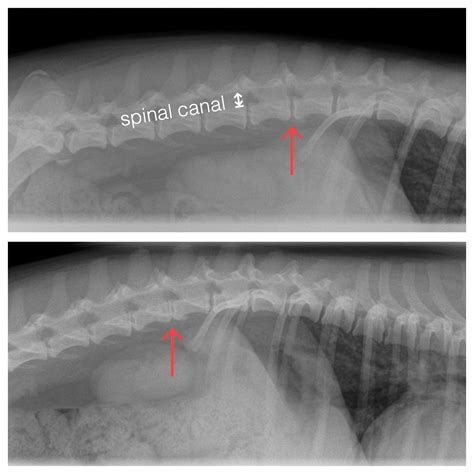

Diagnosing Canine Intervertebral Disc Disease involves a combination of physical examination, medical history, and diagnostic tests. The veterinarian will perform a thorough neurological examination to assess the dog's reflexes, muscle tone, and coordination. Additional diagnostic tests may include:

• X-rays: To visualize the spine and identify any abnormalities or fractures.

• MRI or CT scan: For a more detailed view of the spinal cord and intervertebral discs.

• Myelogram: A dye is injected into the spinal canal to highlight any compression or narrowing.